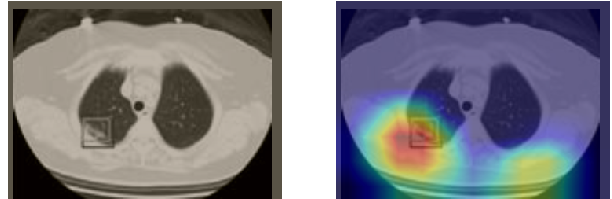

In order to make our models more transparent and provide detailed visual analysis, we present the Grad-CAM localization maps obtained by different models. We consider CT images with COVID-19 abnormalities from the test set of each dataset and highlight the important regions considered for the prediction. For the SARS-CoV-2 dataset we use the Inception V3 model. Figure 13 shows the original CT images and their localization maps. Our model is capable to detect regions that show abnormalities in the CT scans.

In a similar way, we consider classifying the test CT scans from the COVID-19 dataset by the DenseNet169 model and highlight the important regions considered for predictions. We present the original CT images and their localization maps in Figure 13. We can also see that our model is capable to detect the COVID-19 related regions as marked (small square in some images) by expert radiologists.

A wide variety of typical and atypical CT abnormalities have been reported for COVID-19 patients in various studies [58, 59]. So, we tested our models on external CT images extracted from these two publications as they feature typical findings of COVID-19 pneumonia marked by specialists. In order to make sure that not any of the extracted images are unintentionally included in our datasets, specifically the COVID19-CT dataset, we use the model trained on the SARS-CoV-2 dataset. First, the InceptionV3 model is employed to classify the extracted CT images. The model is able to correctly classify the given CT images as COVID-19. Second, in order to interpret the model’s generalization capabilities, we apply the Grad-CAM technique to visualize the regions of abnormalities that are considered. By assessing the different CT images in Figure 15, we can see that the model accurately localizes the disease-related regions. Even more interesting is the fact that the model ignores any specific marks in the images like letters and only localizes the COVID-19 related regions. These visual explanations show the success of our models to learn relevant, generic visual features related to COVID-19 and are capable to correctly classify CT images outside the datasets on which they are trained.